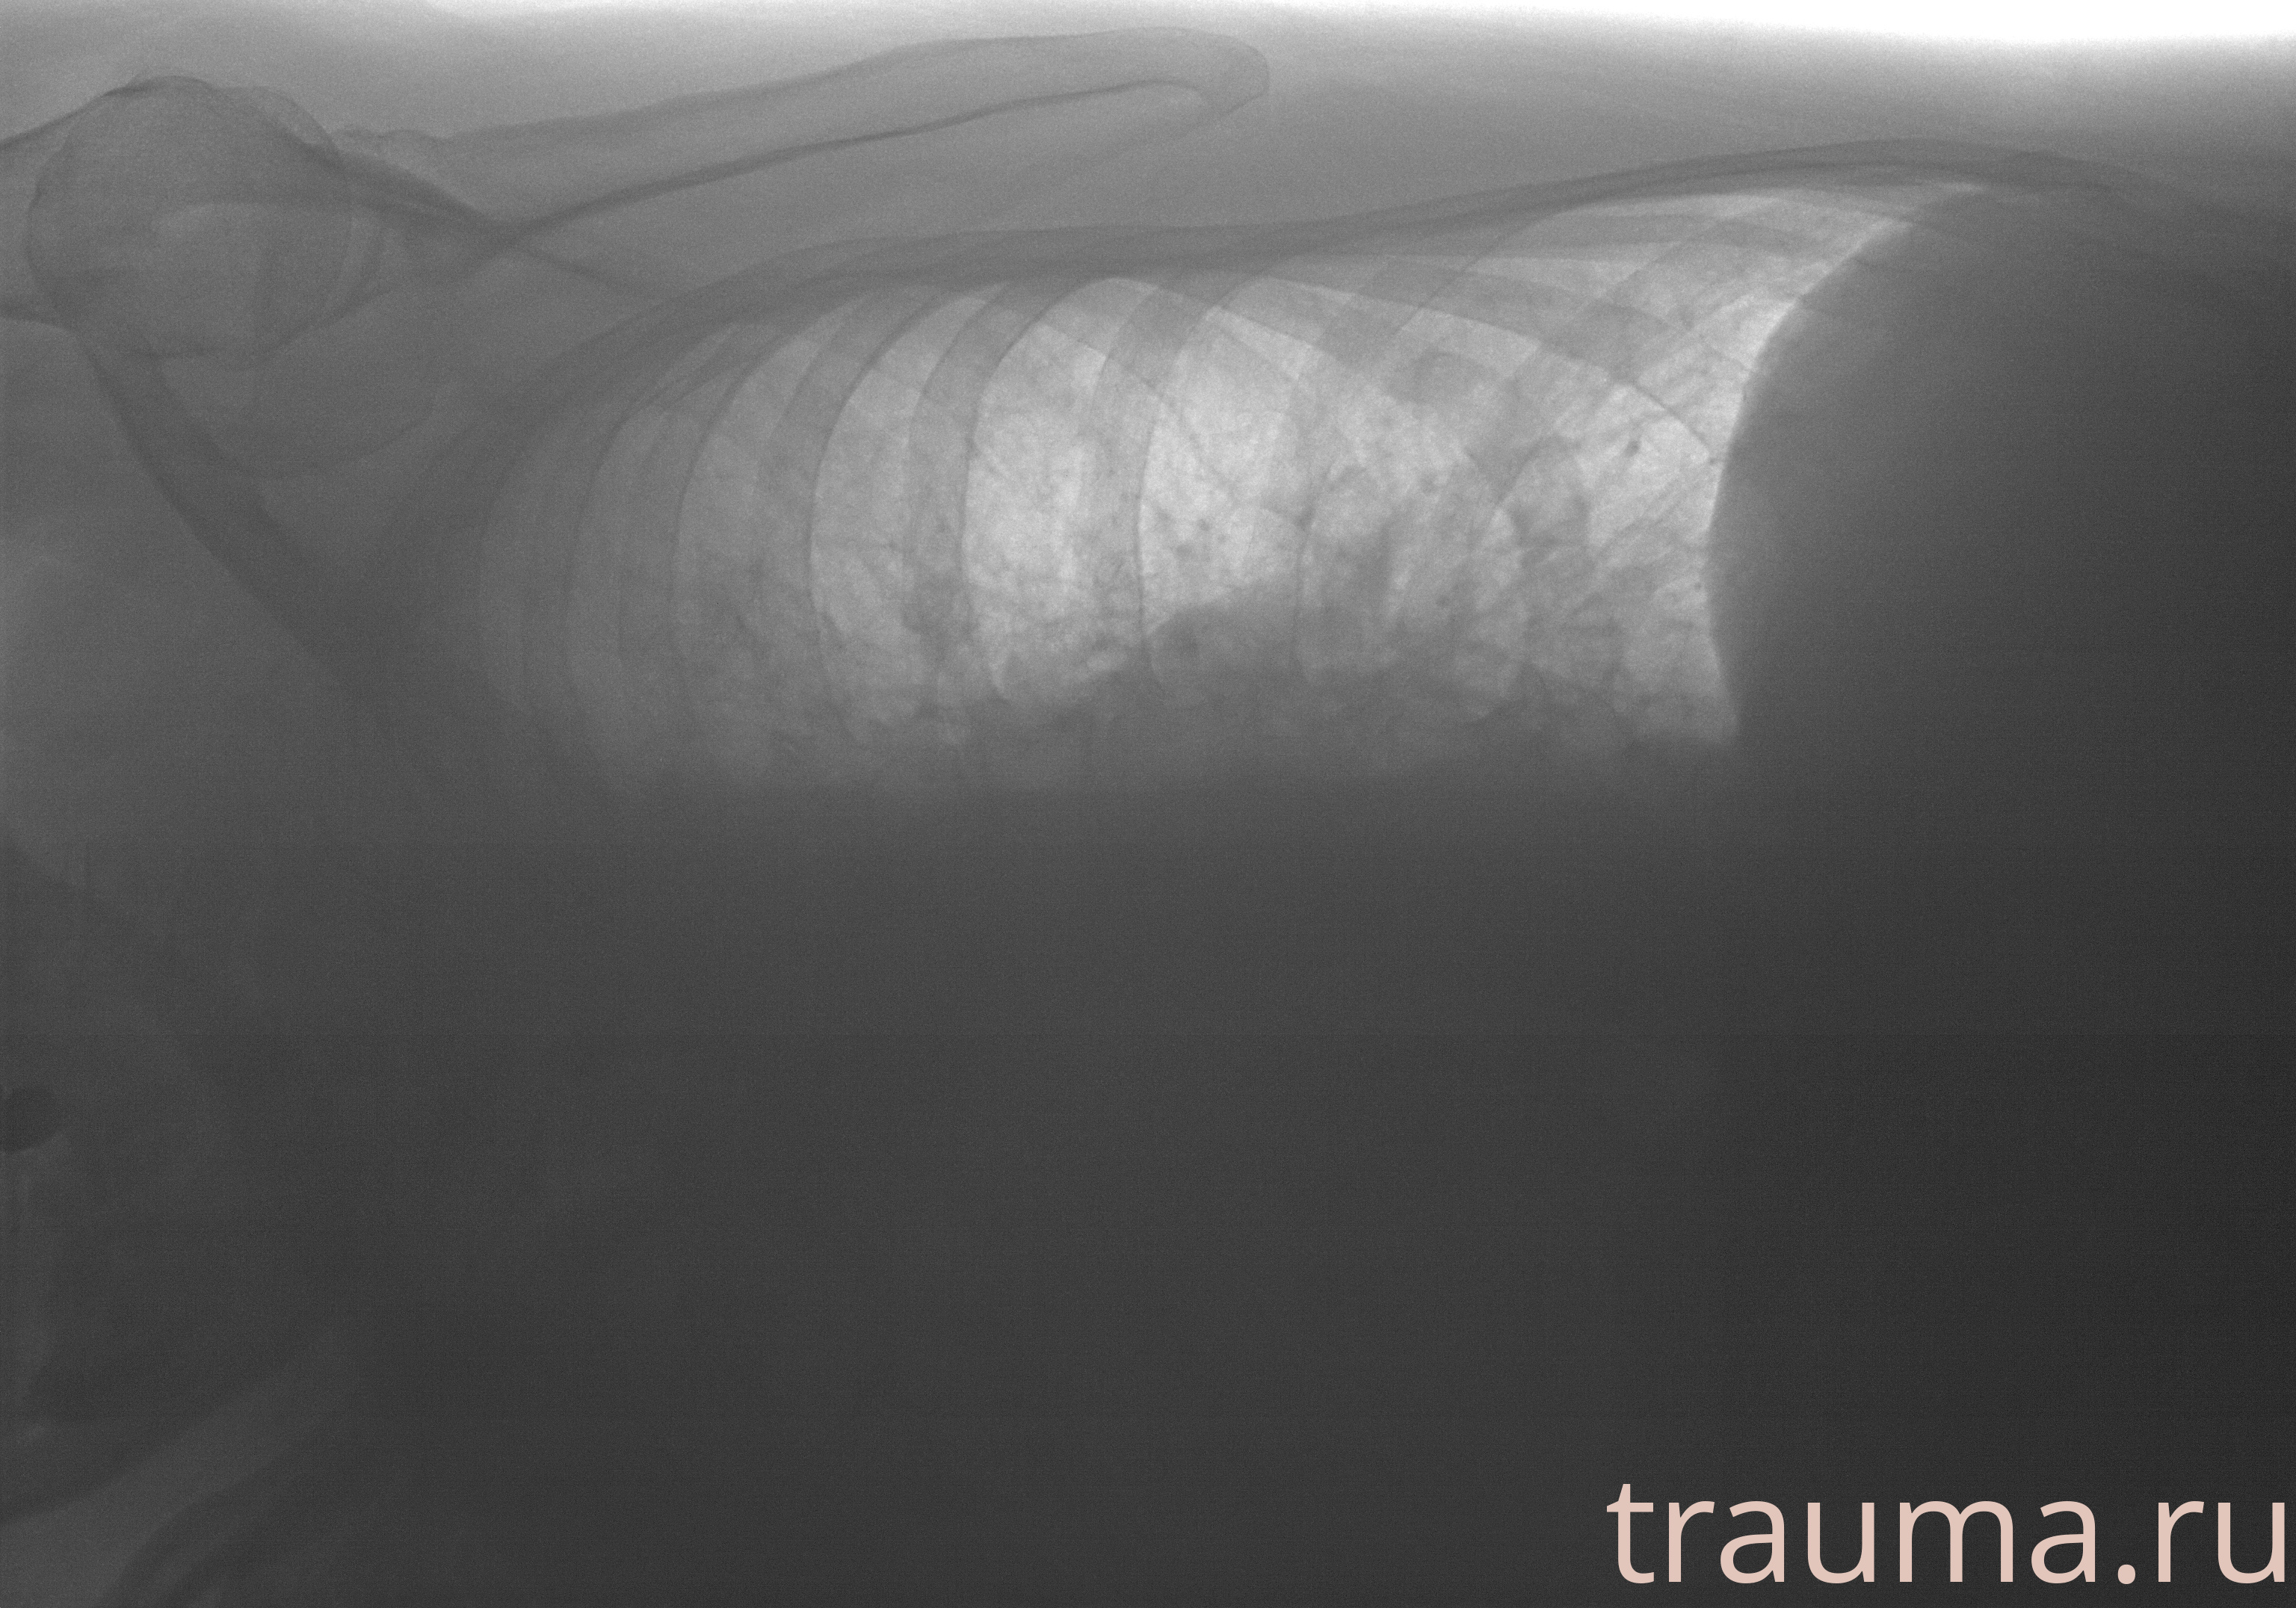

Рентгенограммы

Рентген на дому: по вашему адресу приезжает врач-рентгенолог, травматолог-ортопед с мобильным рентгеновским аппаратом, проводит диагностику травмы или заболевания, делает необходимые рентгенограммы, дает рекомендации по дальнейшему лечению. Получить качественные снимки в домашних условиях возможно благодаря уникальной методике, разработанной МосРентген Центром для института  Склифосовского

Яркость: 1   Контраст: 1   Инвертировать: 0 Увеличение: 1

Перетаскивайте мышь вверх/вниз для контраста, влево/право для яркости. Прокрутка колесом изменяет масштаб. Нажмите Сбросить для возврата к исходному изображению. При увеличении держите мышь в той области, которую хотите рассмотреть.